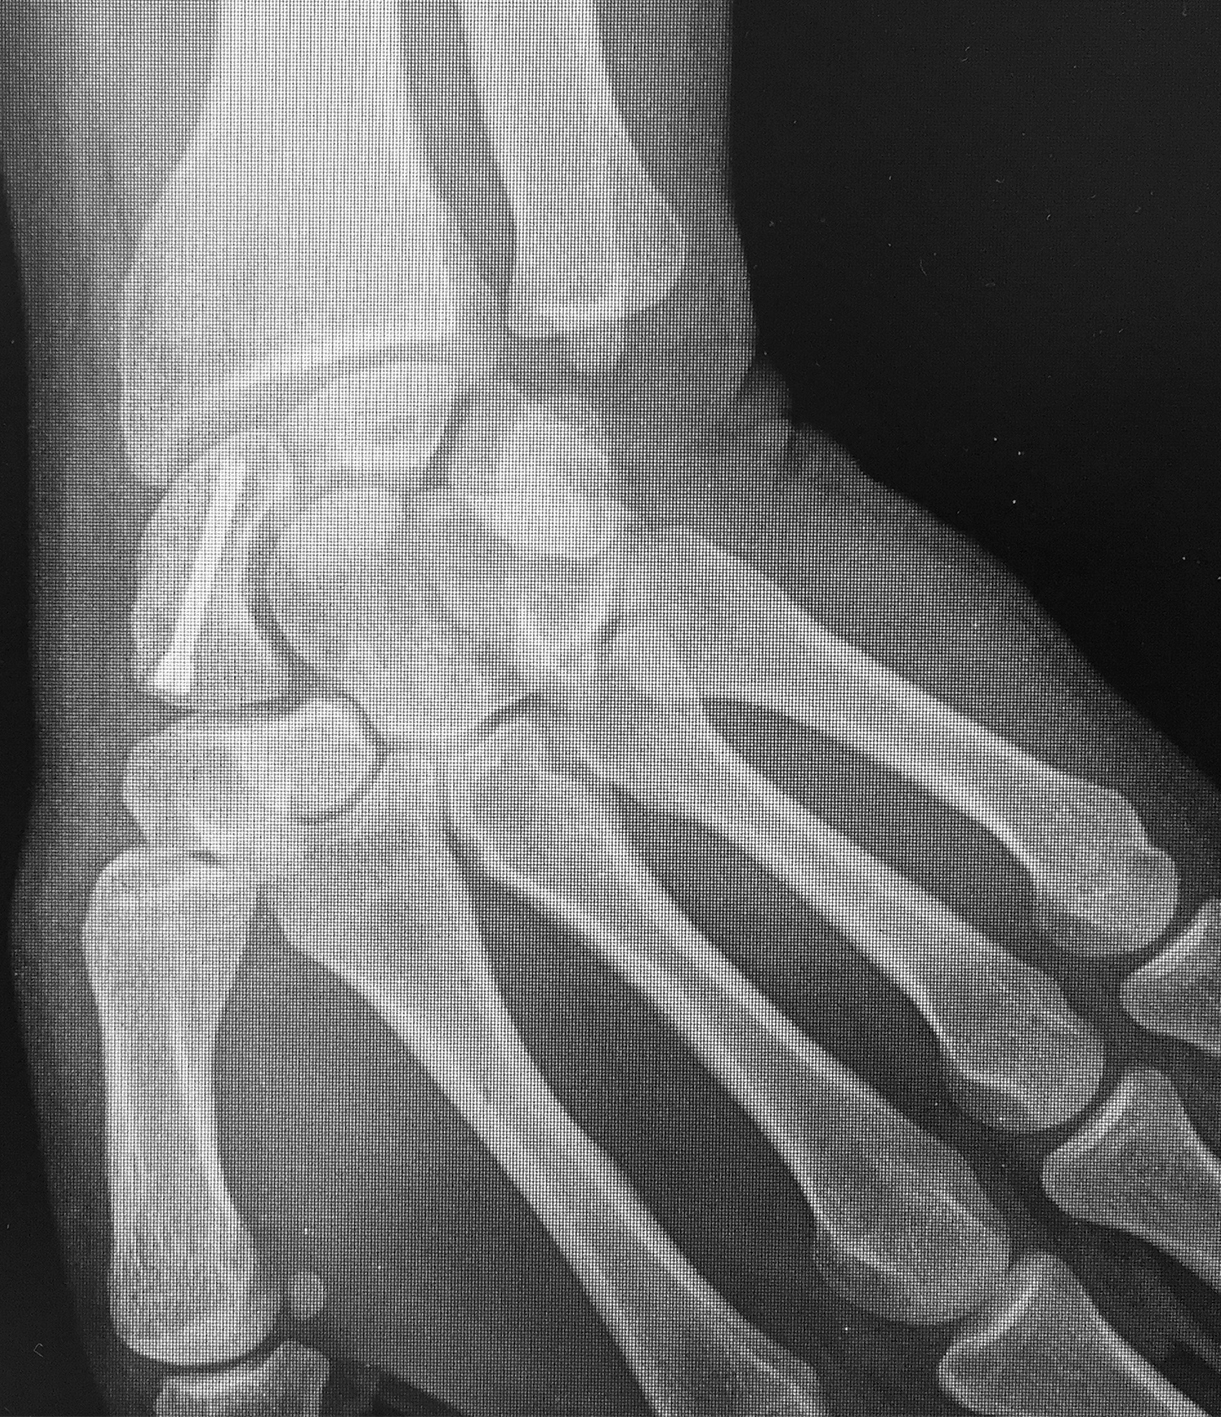

Efectuamos un abordaje volar dado que conserva la vascularización dorsal, permitía la visualización directa del foco, movilización de los polos y manejar la deformidad en joroba mediante el injerto trapezoidal (1)(11)(12). Nos centramos sobre el tendón palmar mayor, efectuando una incisión curvilínea dirigida hacia el tubérculo del escafoides. Se protegió la rama sensitiva cutánea del nervio radial y disecamos el plano superficial incidiendo la cápsula longitudinalmente sobre el eje del escafoides. Se reflejó la cápsula, se identificó el polo distal y proximal colocando dos agujas de Kirschner, a modo de joystick. Cureteamos el foco con una fresa (Figura 1). Dejando el escafoides, extrajimos un injerto cortico-esponjoso trapezoidal de cresta iliaca (Figura 2). Volviendo a la mano, distrajimos los fragmentos escafoideos y colocamos el injerto, con su base en situación volar, para extender el escafoides (1)(5)(12)(13). Colocamos otra aguja de Kirschner retrógrado como guía, y tras medir y mechar, colocamos un tornillo de compresión interfragmentaria (11), para proceder posteriormente a cerrar la cápsula y los planos superficiales. Se colocó una inmovilización con férula de yeso, incluyendo el primer dedo, que mantuvimos durante 4 semanas.

La evaluación de la movilidad mostró que 5 pacientes (29,4%) tenían la movilidad completa; 11 pacientes (64,7%) la conservaron entre el 75 y el 99 % y un paciente (5,9%) entre el 50 y el 74%. No encontramos asociación estadística entre la movilidad y el retraso terapéutico (p=0,241). (Figura 3) (Figura 4) (Figura 5) (Tabla 1) (Tabla 2).

Figura 4: Caso 12

a) Radiografía de frente pre-operatoria

b) Radiografía pre-opertaoria, enfoque de escafoides

c) Radiografía post operatoria

e) 24 meses de seguimiento. Radiografía de frente

f) 24 meses de seguimiento. Radiografía de perfi

g) 24 meses de seguimiento, extensión de muñeca

h) Flexión de muñeca